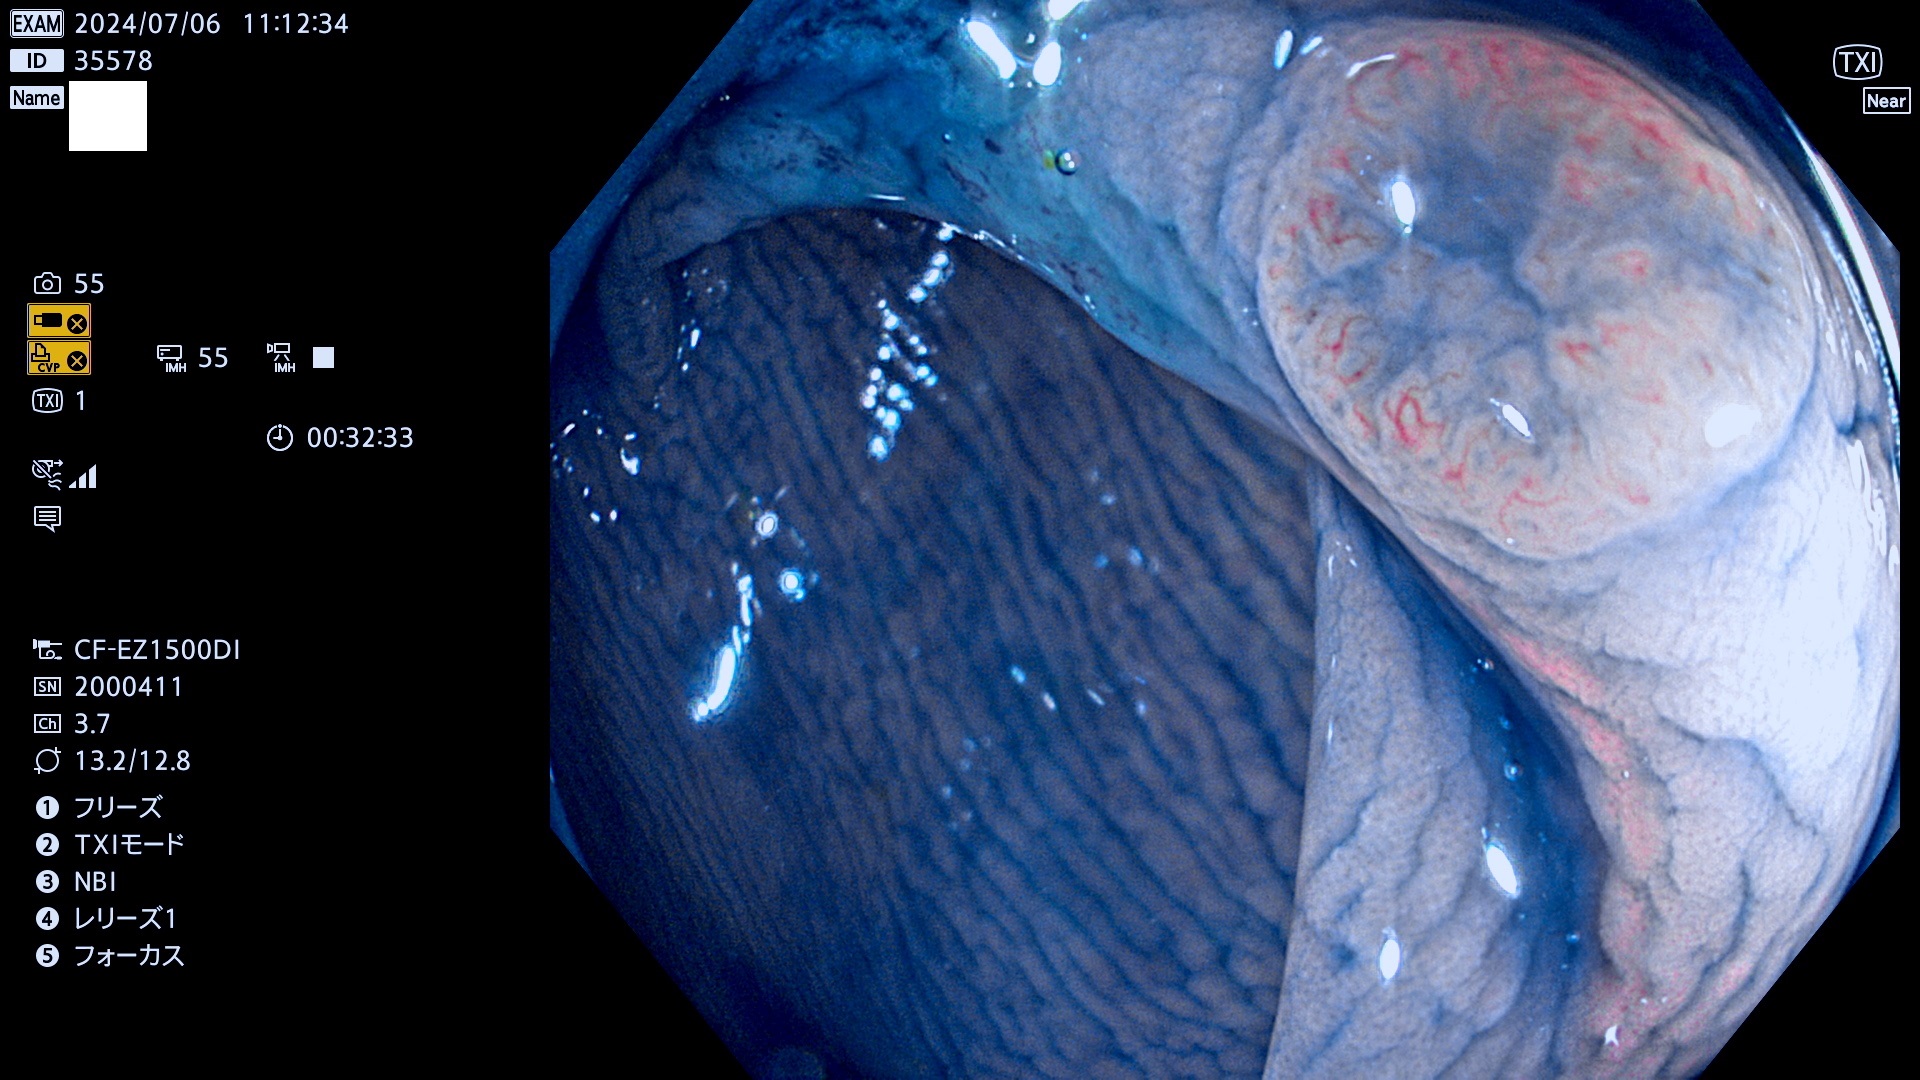

今週のUb、Uc型腺腫

完全に平坦な物をUb、陥凹している物をUcと呼びます。最も発見が難しく危険な病変です。

毎週の検査(木・金・土・日)に発見されたUb、Uc型・腺腫を、その週の日曜の夜にUPし1週間、提示します。

抽出の対象期間 2024年7月4日〜7月14の8日間(50件の検査)4件 (4/50=8%)